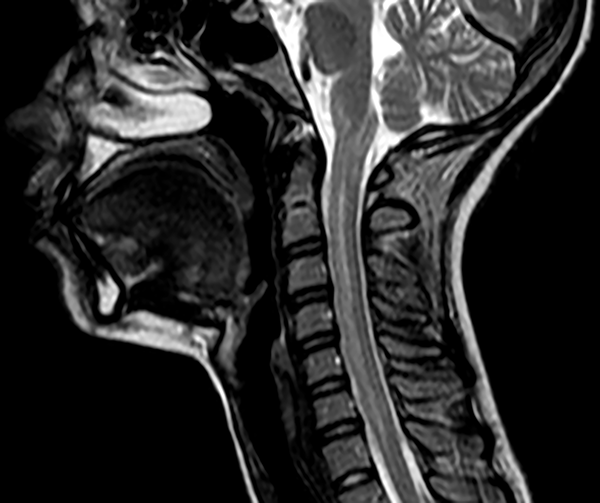

El resultado de la ecografía renovesical informó imagen hipoecogénica de 43 x 46 x 31 mm. En RMN de abdomen con contraste se evidenció masa ocupante de espacio paraaórtico de gran tamaño (fig. 3). Seguidamente se solicitó dosaje de catecolaminas en orina y suero que arrojaron valores elevados 10 veces por encima de la normalidad confirmando el diagnóstico presuntivo de feocromocitoma.

Figura 3. Imagen de resonancia magnética de abdomen con contraste. Se observa masa ocupante en zona del espacio paraaórtico.